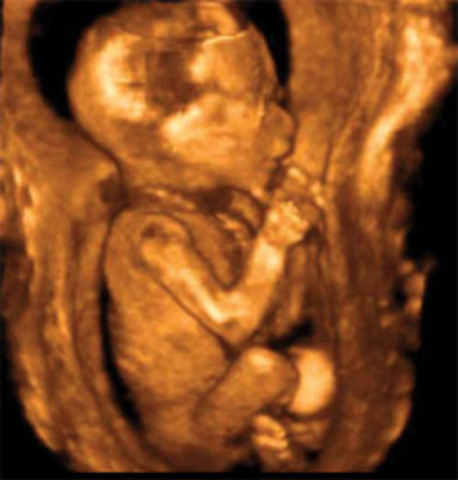

• week 29 of the fetal development

week 29 of the fetal development

The bones are fully developed but soft. The fettus can suck his thumb.